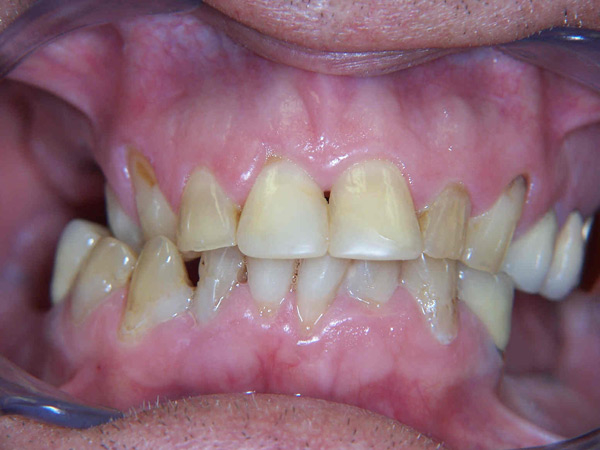

Case Study 14

Problem: This young man was hit by a car while riding his bike. He had multiple fractures in his jaw and three front teeth were fractured.

Plan: Our plan… his fractures were fixed. The trauma left a bony defect which was grafted as well as soft tissue VIP grafts. Placed three separate implants with guided surgery. Molded the tissue and placed Zirconium abutments with porcelain crowns.

A great young man with a confident smile.